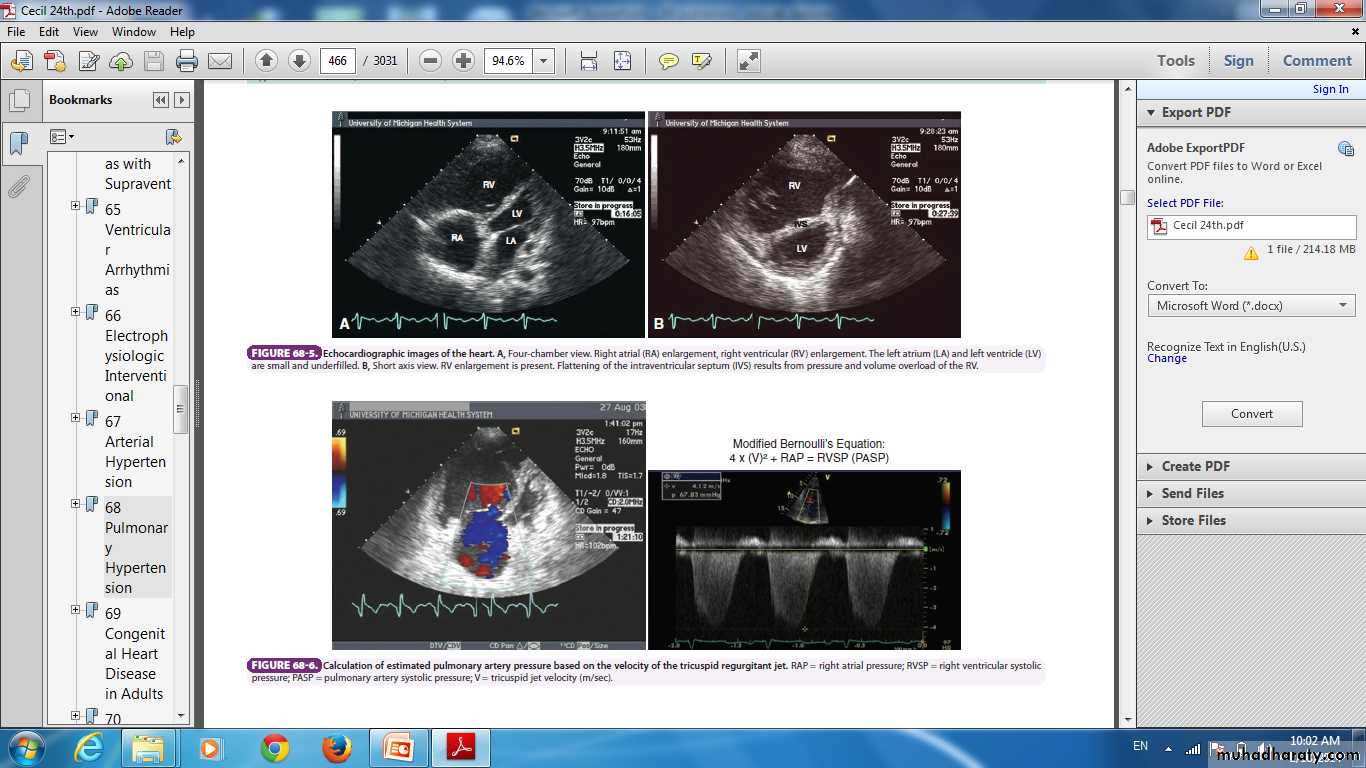

Chest X-ray ,ECG , Echocardiography .

Electrocardiogrm demonstrating sinus rhythm, right axis deviation, and right ventricular hypertrophy with a strain pattern.

Posterior-anterior (A) andLateral (B) chest radiographs demonstratingenlarged proximal pulmonary arteries andright ventricular enlargement